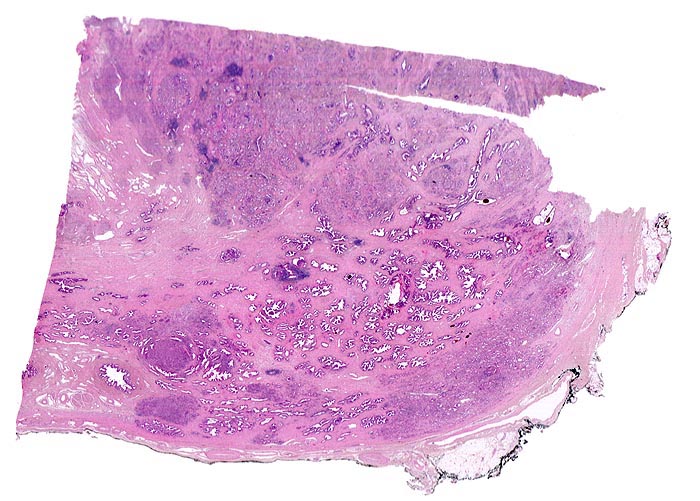

Makroskopie:

Prostatakarzinome sind häufiger in der Aussenzone lokalisiert, während die benigne Prostatahyperplasie gehäuft den Mittellappen betrifft. Makroskopisch imponieren Karzinome als periphere, gelbe, harte Areale.

Morphologische Merkmale:

• Normale Prostatadrüsen mit grossen Lumina angeordnet in Läppchen. Das Epithel bildet Falten und besteht aus einer inneren hochprismatischen sekretorischen Zellschicht und einer äusseren Schicht flacher Myoepithelien.

• Herde kleiner Karzinomdrüsen ohne Basalzellschicht.

• Fehlende lobuläre Anordnung der Karzinomdrüsen.

• Konfluierende Drüsen bilden kribriforme Muster.

• Karzinomzellen mit stark erhöhter Kern-Zytoplasmarelation und hyperchromatischen Zellkernen mit grossen eosinophilen Nukleolen.

• Wenig differenzierte Karzinomanteile ohne erkennbare Drüsenbildung.

• Perineuralscheideninvasion.

• Links oben im Präparat finden sich Anteile der Samenblase mit polymorphem Epithel und gelben Lipofuszinpigmenteinlagerungen.

• Unterhalb der Samenblase sind von flachem Endothel ausgekleidete Lymphgefässe mit Karzinominfiltraten erkennbar (Lymphangiosis carcinomatosa).

• Der mit schwarzer Tusche markierte Resektionsrand in der unteren Hälfte des Präparates ist tumorfrei.